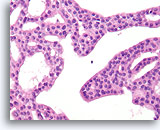

Papilloom, Borst FNA, Celblok.

Deze afbeelding van dezelfde FNA als in afbeelding 18 bevat een duidelijk papillaire architectuur.

10X

Papilloom, Borst FNA, Celblok.

Deze afbeelding van dezelfde FNA als in afbeelding 18 bevat een duidelijk papillaire architectuur.

10X

Papilloom, Borst FNA, Celblok.

Met een sterkere vergroting kan een gemengde celpopulatie gezien worden die het oppervlak en de onderliggende melkgangen bekleden. Een rij myoepitheliale cellen is zichtbaar tussen de ductale cellen en het onderliggende stroma (pijl). Let op de spleetachtige ruimte die kenmerkend is voor typische hyperplasie (open pijl).

40X

Papilloom, Borst FNA, Celblok.

Met een sterkere vergroting kan een gemengde celpopulatie gezien worden die het oppervlak en de onderliggende melkgangen bekleden. Een rij myoepitheliale cellen is zichtbaar tussen de ductale cellen en het onderliggende stroma (pijl). Let op de spleetachtige ruimte die kenmerkend is voor typische hyperplasie (open pijl).

40X

Papilloom, Borst FNA, Celblok.

Let op de bijmenging van bleke myoepitheliale cellen (pijlen) en de rijping van de ductale cellen wanneer zij zich verder van het basaalmembraan stratificeren (open pijl).

40X

Papilloom, Borst FNA, Celblok.

Let op de bijmenging van bleke myoepitheliale cellen (pijlen) en de rijping van de ductale cellen wanneer zij zich verder van het basaalmembraan stratificeren (open pijl).

40X